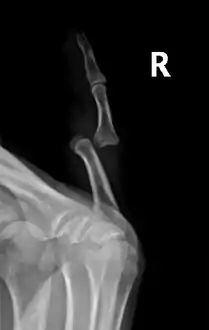

Radiograph of right fifth phalanx bone dislocation

Radiograph of left index finger dislocation

Radiograph of right fifth phalanx dislocation resulting from bicycle accident

Right fifth phalanx dislocation resulting from bicycle accident